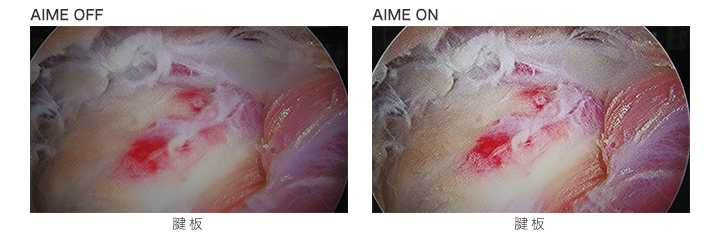

A.I.M.E.画像処理への印象は?

例えば、焦点の合っていない部分も、A.I.M.E機能によって焦点が合ったように見え、組織の起伏形状までが分かるようでした。この画像処理によって、映像に奥行きを感じました。A.I.M.E.の長所は、術者にとって組織を立体的に感じさせ、そして組織の形状を把握し易くなり、操作上のストレスが軽減される点です。さらに画像処理による表示の遅延はまったく感じず、私の手技に追従していました。

例えば左の写真のように、手前付近に白い組織があるとそれがハレーションを起こしてしまい、見にくくなってしまうが、A.I.M.E.機能では、ハレーションが抑えられ、確認したい 箇所が見やすくなり、処置がしやすくなったと感じました。

また上の写真では少し分かりづらいですが、組織奥側が暗くて見えづらい場合など、難渋する症例が多いですが、A.I.M.E.画像処理では、奥の深いところも明るく見えました。重要な組織の境界部分の判断や処置方針の決定のための情報が得られやすくなり、即ち術者の手技の効率を高め、処置時間短縮の可能性が期待できそうです。

A.I.M.E.™ (Advanced Image Multiple Enhancer)は、内視鏡カメラなどからの医療画像を内蔵画像処理技術(ハードウェア処理)により、高速に、コントラストや色を強調できるソニーの独自の技術です。従来のエッジをシャープにする強調とは異なり、構造物自体を強調します。